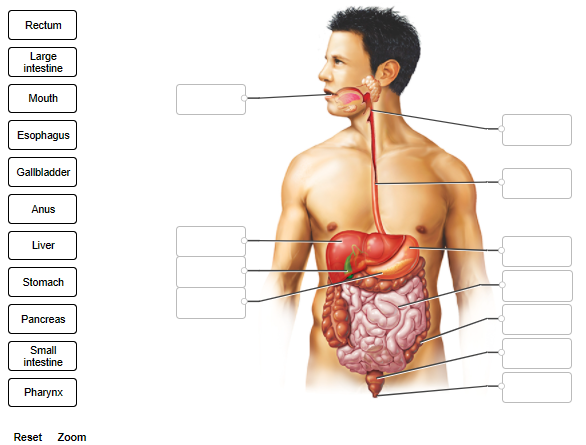

Label only the organs of the digestive system that comprise the alimentary tract.

Before looking at diagnostic images, take a moment to identify digestive organs in the illustration.